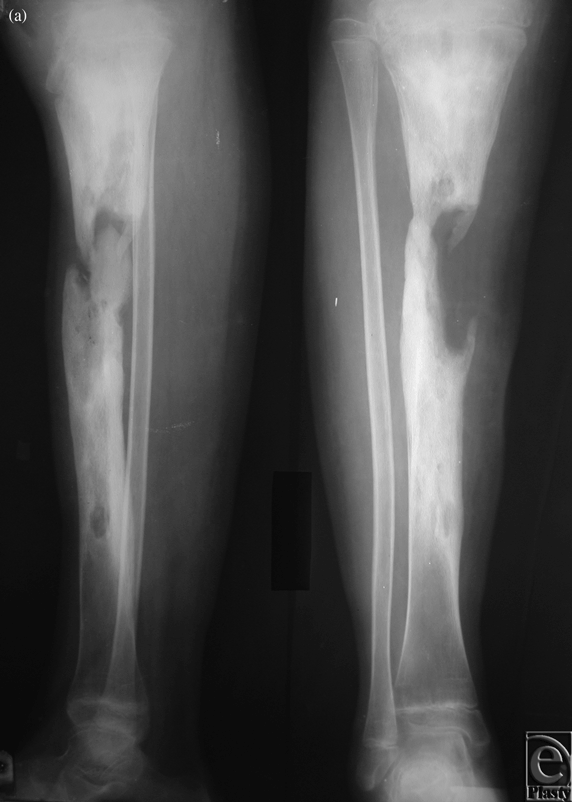

Case 3: Osteomyelitis of the lower leg

The patient was a 28-year-old man who suffered from hematogenous osteomyelitis of the tibia. Before being transferred to our center, he underwent 4 separate debridements. After a 23-cm-long space between the 2 ends of the affected tibia was obtained by Ilizarov external fixation in our hospital, a free fibula osteoseptocutaneous flap was harvested and transferred to cover both the bone and the soft tissue defect. The external fixator was removed 8 months after the free flap transfer (Figs 3a-3e).